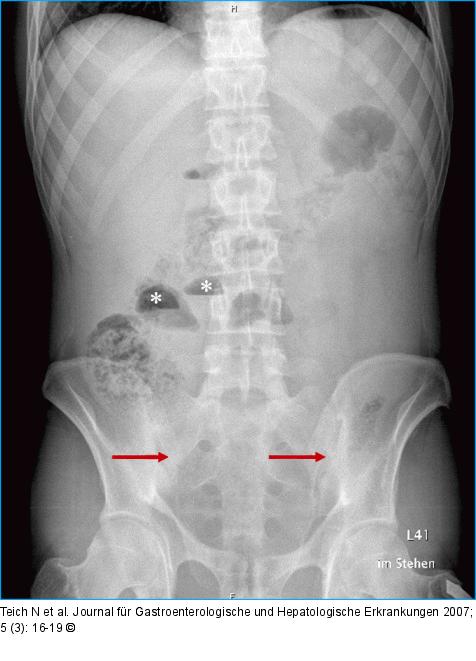

Abbildung 2: Dünndarmspiegel Dünndarmspiegel (Sterne) als Zeichen des mechanischen Ileus. Nebenbefundlich Spondylitis ankylosans (Pfeil). |

Dünndarmspiegel (Sterne) als Zeichen des mechanischen Ileus. Nebenbefundlich Spondylitis ankylosans (Pfeil). |